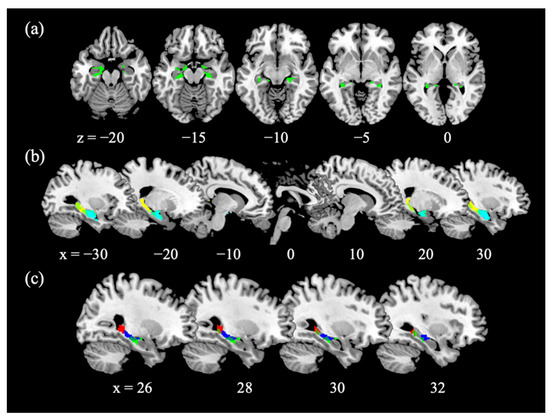

3.2. Age-Related Decreases in Hippocampal Gray Matter Volume (GMV)

3.3. Age and Hippocampal Activation in Reactive and Proactive Inhibitory Control

3.4. Age-Related Structural and Functional Changes in the Hippocampus